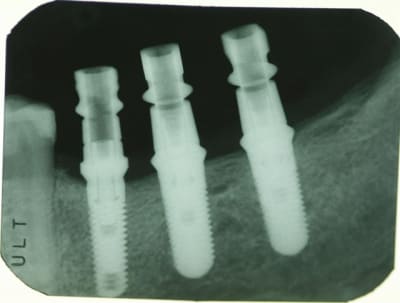

Radio d'un cas ID (Implant Direct) # 36 et 37,

et Zimmer TSV #35.

J'aime bien les ID (copie de Zimmer)

J'ai posé 30 Zimmer et 25 Implant Direct en 2008.

Le $ des ID est très bon, pillier inclus.